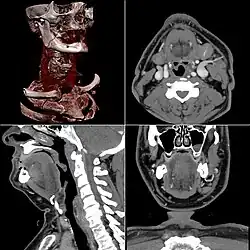

КТ-ангиография

КТ-ангиография позволяет получить послойную серию изображений кровеносных сосудов; на основе полученных данных посредством компьютерной постобработки с 3D-реконструкцией строится трёхмерная модель кровеносной системы.

Спиральная КТ-ангиография — одно из последних достижений рентгеновской компьютерной томографии. Исследование проводится в амбулаторных условиях. В локтевую вену вводится йодсодержащий контрастный препарат в объёме около 100 мл. В момент введения контрастного вещества делают серию сканирований исследуемого участка.